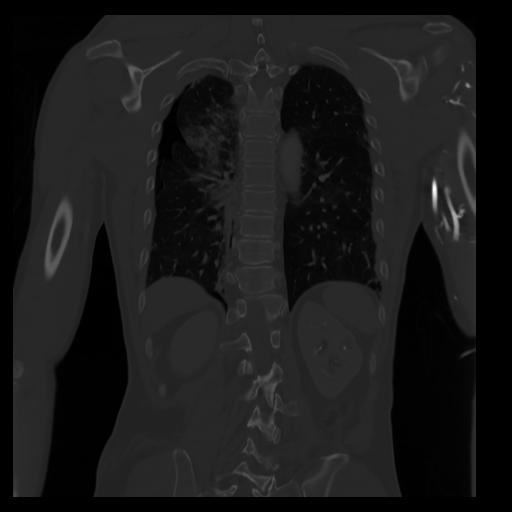

29 CUERPO,CE,Coronal,3.000,CUERPO,Coronal,